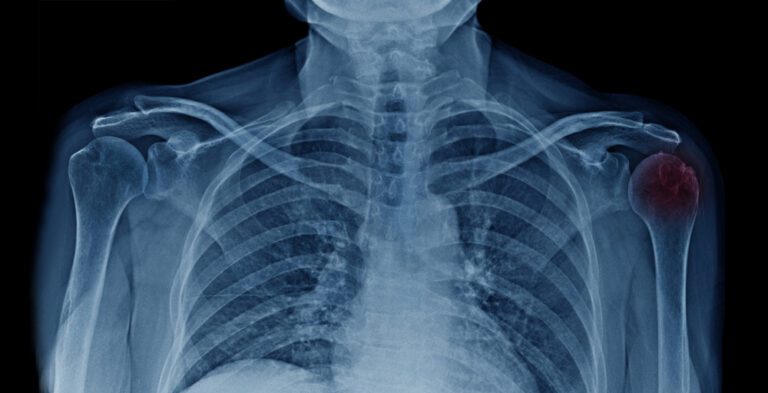

As bursas são pequenas bolsas repletas de líquido que recobrem as proeminências ósseas no corpo humano. Sua função é proteger os tendões e, principalmente, reduzir o atrito quando o músculo desliza pelo osso. Porém, quando essas estruturas estão inflamadas, tem-se o que se chama de bursite.

A bursite no ombro é a inflamação das bursas que recobrem o manguito rotador. A bursite tem cura na maioria das vezes, principalmente se diagnosticada no início da lesão e tratada adequadamente. Porém, quando não tratada, ela pode se tornar crônica e causar prejuízo ao movimento dos braços.

O principal sintoma da bursite no ombro é a dor, que muitas vezes se confunde com a da tendinite no ombro ou de outras lesões e síndromes que acometem essa articulação. Porém, a dor da bursite costuma estar localizada na região anterolateral do ombro, podendo irradiar para o braço e chegar ao cotovelo. Além disso, pode se intensificar durante a elevação dos braços, movimento que causa uma compressão da bursa inflamada.

O diagnóstico da bursite no ombro é dado a partir da história clínica e do exame físico realizado pelo ortopedista durante a consulta. Após estabelecer uma hipótese diagnóstica, alguns exames de imagem, como a ultrassonografia ou ressonância magnética, podem ser solicitados para obter a confirmação.